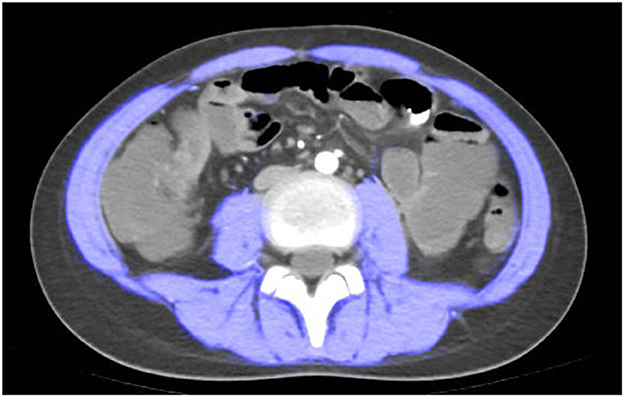

CTE examination was performed following the standard imaging protocol. At the level of the third lumbar vertebra, the boundaries of skeletal muscles were manually outlined using ImageJ software version 1.54p (35). Throughout the study, the boundaries of skeletal muscles were determined by trained radiologists. Pre-defined radiation attenuation ranges are used to demarcate muscle (-29 Hounsfield units to +150 Hounsfield units) (see Figure 1). Calculate the skeletal muscle area (SMA) in square centimeters from the pixel count using ImageJ.

Figure 1. Computed tomography (CT) scan measured at spinal level L3. a patient with sarcopenia (Male, height = 1.55 m, L3SMI 28.67, L3SMI Z-score−2.423).